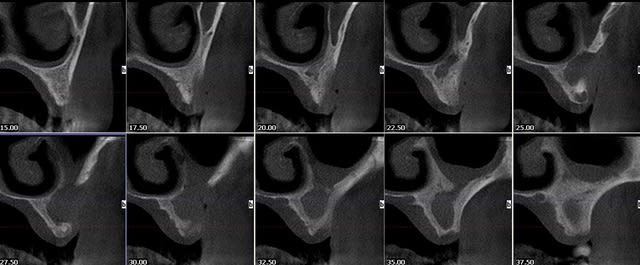

suite à ce cas que j'avais posté

hier fait une rvg de controle sur deux implants posés en 2007 (serf evl+) et en mésial on distingue nettement que l'os s'est formé sur le col lisse...

explications ?

2007 efrvxe - Eugenol

2009 gowarp - Eugenol

j'ai constaté aussi un peu la même chose sur ce cas (et sur d'autres)

je précise que l'incidence est la même entre les 2 clichés.

c'est plutôt rassurant ces reconstructions osseuses péri-implantaires.